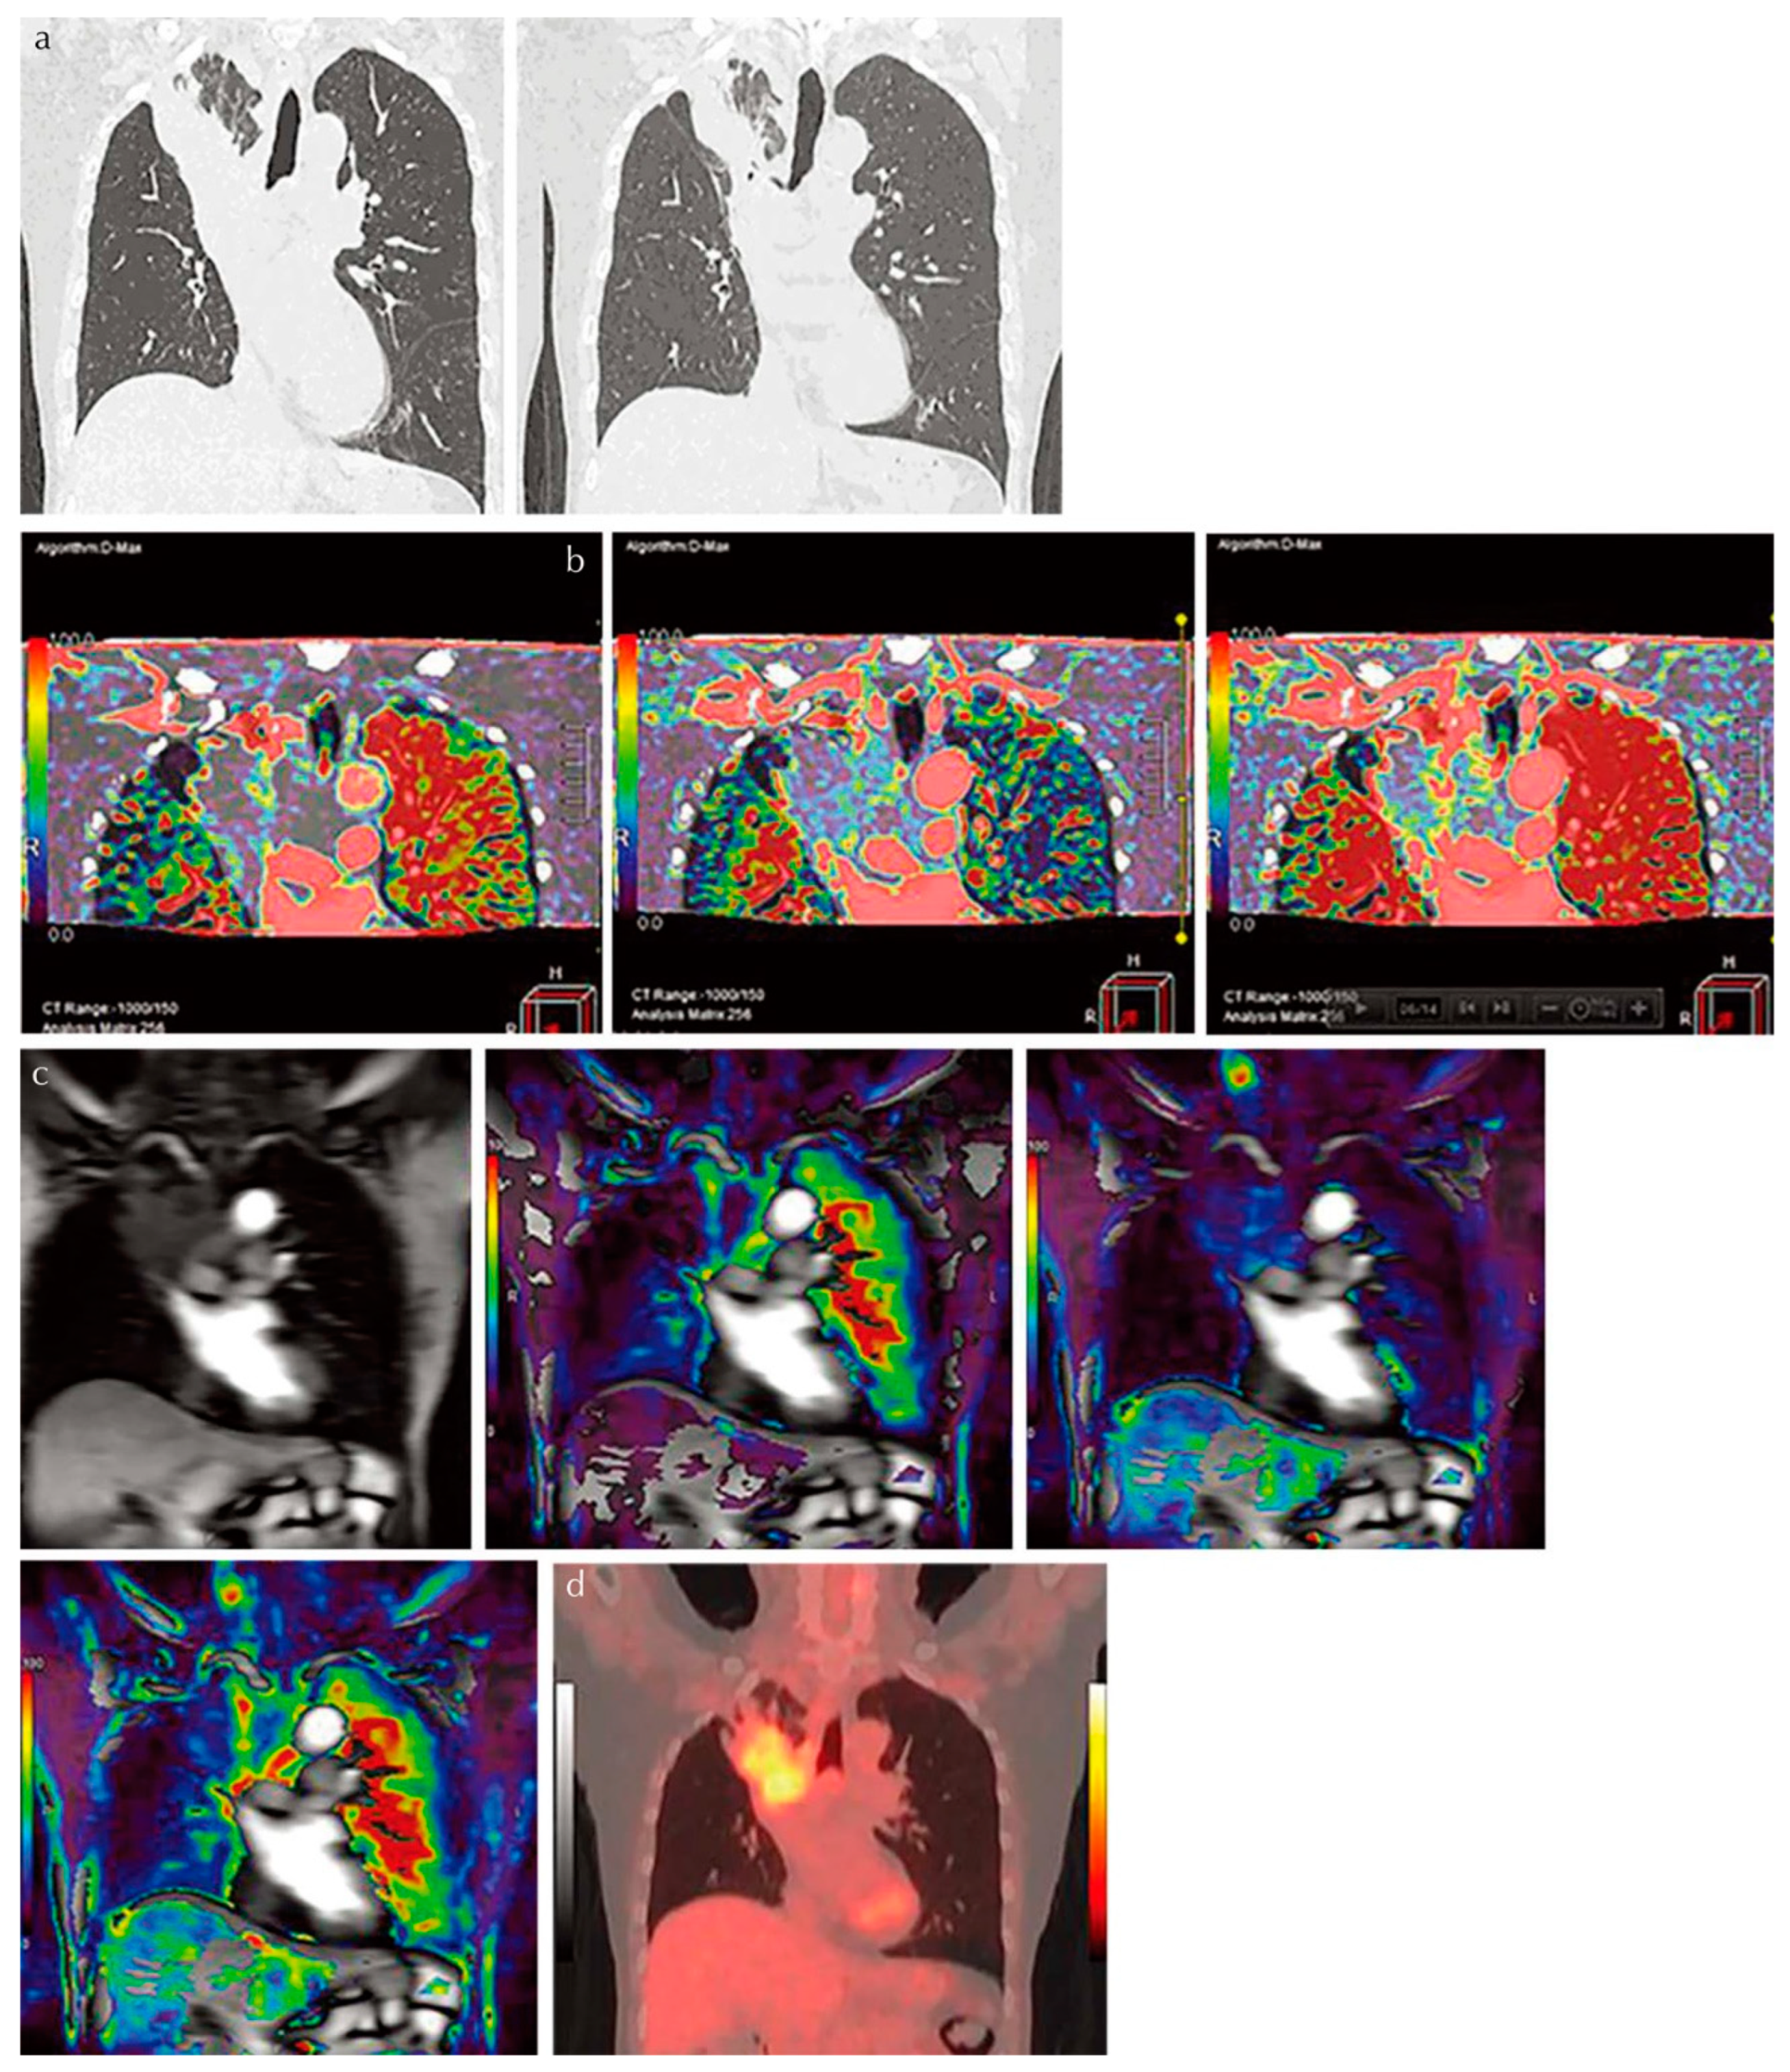

For the diagnosis of pulmonary nodules, the diagnostic performance of dynamic first-pass CE-perfusion ADCT was equal to or significantly better than that of FDG-PET/CT or dynamic first-pass CE-perfusion MRI with a 1.5 T or 3 T MR system [15,21,22] (Figure 3).

Figure 3.

An 81-year-old male patient with squamous cell carcinoma treated with chemoradiotherapy and assessed as NC. Progression-free and overall survivals at 15 and 24 months (permission from reference [22]). (a) Thin-section MPR image derived from thin-section CT data (L to R: MPR images obtained pre- and post-treatment at lung window setting) show lung cancer in the right upper lobe. This case was assessed as NC according to response evaluation criteria for solid tumors (RECIST ver.1.1). (b) Perfusion maps derived from dynamic first-pass CE-perfusion area-detector CT assessed with the dual-input maximum slope method (L to R: pulmonary arterial perfusion, systemic arterial perfusion, and total perfusion maps) for the same targeted lesion. Pulmonary arterial perfusion, systemic arterial perfusion, and total perfusion were 13.6, 18.9, and 32.5 mL/100 mL/min, respectively. This case was assessed as a RECIST-based non-responder for systemic arterial and total perfusions and as true positive. (c) Source image and perfusion maps obtained with dynamic first-pass CE-perfusion MR imaging assessed with the dual-input maximum slope method (L to R: source image, pulmonary arterial perfusion, systemic arterial perfusion, and total perfusion maps) for the same targeted lesion. Pulmonary arterial perfusion, systemic arterial perfusion, and total perfusion were 9.2, 28.9, and 38.1 mL/100 mL/min, respectively. This case was also assessed as a RECIST-based non-responder for systemic arterial and total perfusions and as true positive. However, this case was evaluated as responder and as false positive based on pulmonary arterial perfusion findings. (d) PET/CT shows high uptake of 2-[fluorine-18]-fluoro-2-deoxy-d-glucose, and SUVmax was evaluated as 4.7. This case was evaluated as a RECIST-responder and assessed as false negative. PR, partial response; MPR, multiplanar reformatted; RECIST, Response Evaluation Criteria in Solid Tumors; CE, contrast-enhanced; SUV, standardized uptake value; PET, positron emission tomography.

Moreover, the diagnostic performance of dynamic first-pass CE-perfusion ADCT for lymph node metastasis was also shown to be equal to or significantly better than that of FDG-PET/CT for non-small-cell lung cancer (NSCLC) patients [20]. In addition, the dual-input maximum slope model was found to have better potential for accurate evaluation than the single-input maximum slope or Patlak plot methods in the aforementioned settings [19]. A comparison of the capability of response evaluation criteria to differentiate solid-tumor (RECIST) responders from RECIST non-responders in NSCLC patients treated with conservative therapy showed no significant differences in the sensitivity, specificity, and accuracy of dynamic first-pass CE-perfusion ADCT, MRI analyzed with the same dual-input maximum slope model, or FDG-PET/CT [22]. Furthermore, hybrid-type IR was shown to be more effective than FBP in terms of dose reduction for dynamic first-pass CE-perfusion ADCT while maintaining image quality and reducing measurement errors [16]. Dynamic first-pass CE-perfusion ADCT with an appropriate mathematical model as well as a reconstruction method, therefore, merits use as a pulmonary functional imaging method in routine clinical practice. Furthermore, Canon Medical systems is now developing and testing an appropriate protocol and proprietary software for the analysis of whole-lung dynamic first-pass CE-perfusion ADCT data and the creation of a whole-lung perfusion parameter map for a variety of different academic and clinical purposes, which will be made available for use in the near future.